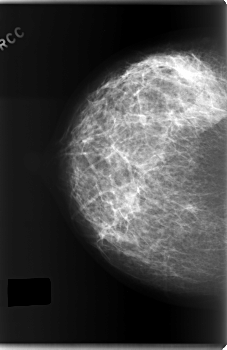

C_0203_1.RIGHT_CC

RIGHT_CC LINES 5936 PIXELS_PER_LINE 3856 BITS_PER_PIXEL 12 RESOLUTION 50 NON_OVERLAY